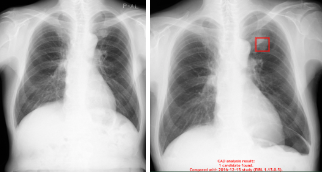

当院では、胸部レントゲン検査においてAI読影支援ソフトの導入を予定しています。

AIが画像の中から病変の可能性がある部分を「確認ポイント」として示し、

医師がその上で丁寧に画像を確認することで、病変の見逃しリスクをできるだけ減らす診療体制を整えています。